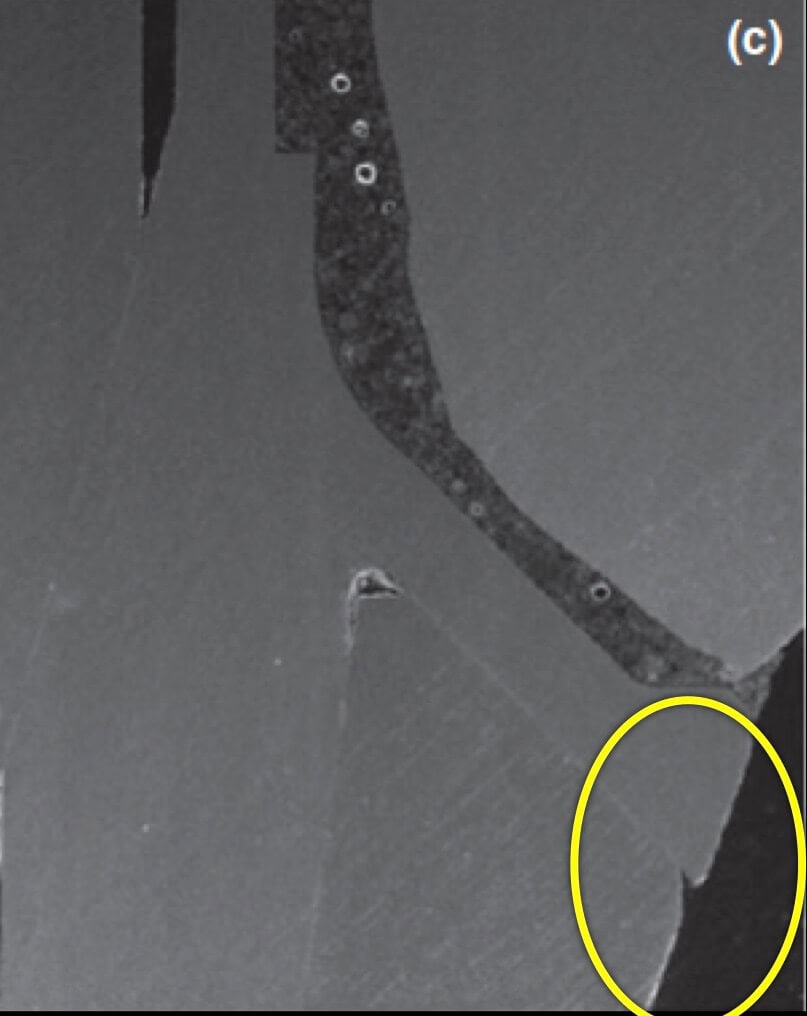

- too shallow implant placement. This is very commonly encountered in the upper anterior sites, where the implant is typically to be placed below the mesial and distal bone margins (a).

- too palatal placement, again very common in the upper anterior sites, where the bone resorption pattern eliminates much of the buccal ridge (b) (Photo courtesy Dr. M Janda).

- too palatal angle of placement (c).

- wrong mesio-distal position (c).